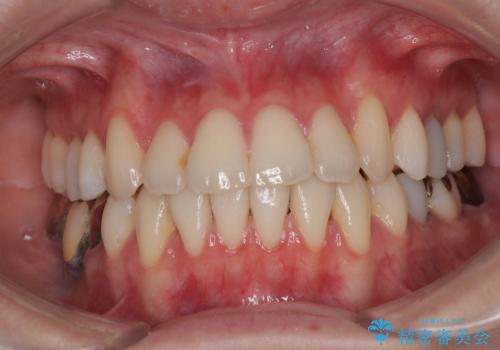

【モニター】前歯のデコボコをインビザラインで綺麗に

- 上下前歯のデコボコとクロスバイトを気にして来院された患者様です。

治療済みの処置歯が多いため、インビザラインを用いて矯正治療を行うこととしました。

下顎臼歯部にブリッジが装着されており、移動不可のため、IPR(歯と歯の間を削る)と歯列全体を拡大させることで、歯並びを整えていくこととしました。

インビザライン特有の奥歯の噛みにくさが治療後半に発現しましたが、無事に終了させることができました。